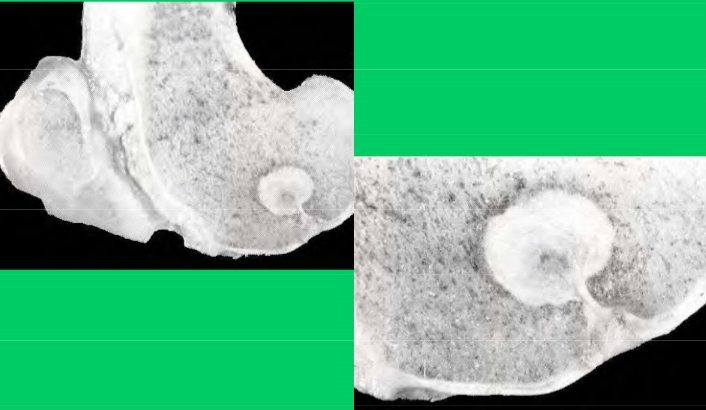

What is the location and lesion

This is an OCD cyst in the medial condyle of a horses femur- the only reported location